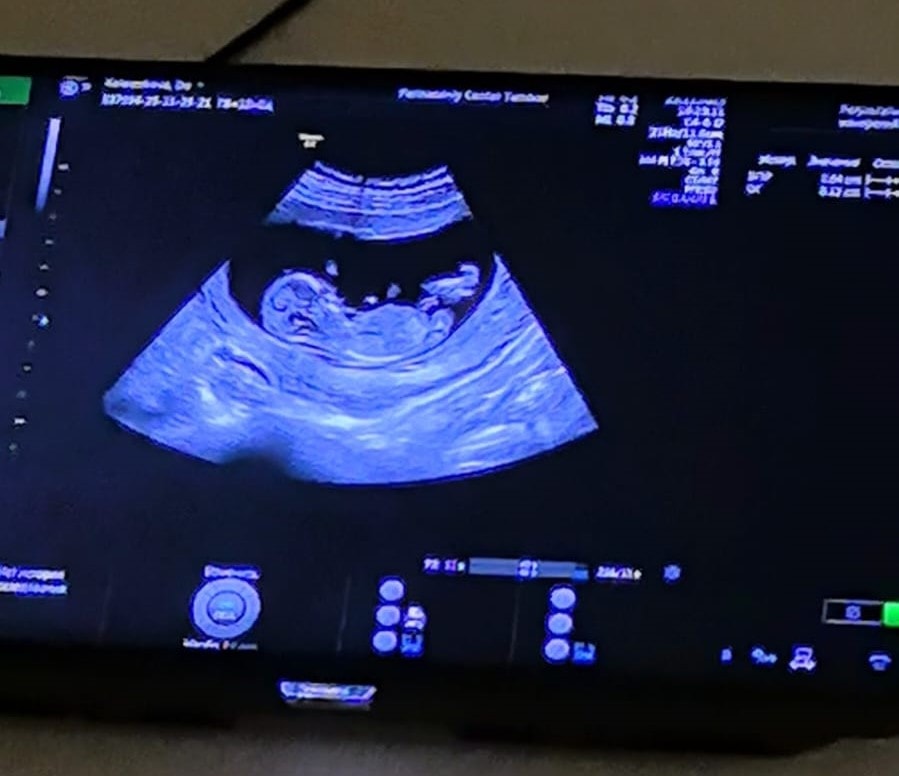

Узи и первый скрининг. Пол??

Анализы, скринингиВот и прошел наш первый скрининг. С человечком все хорошо, махал ручкой. Все соответствует нормам. Получилась такая картиночка. Кто разбирается, предположите пол, очень интересно.) +в комментарии

Мальчик , но фото не очень, поскольку половой бугорок не понятен.По черепу мальчик.

Тут не видно полового бугорка к сожалению , может есть другие снимки …. А так гадать только ) мне интуитивно девочка кажется 👐🏻🌷